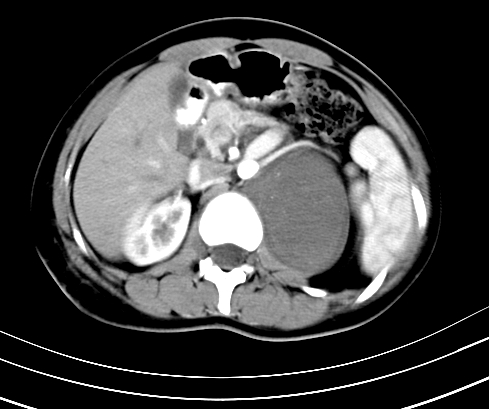

腹部平扫

动脉期